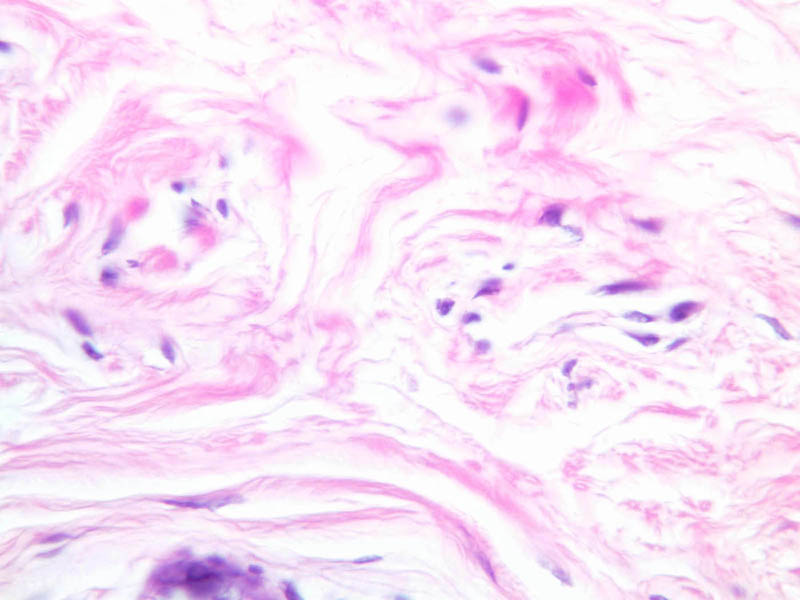

Dense connective tissue The dense connective tissues contain more numerous and thicker fibers, but considerably fewer cells. The primary cell type of the dense connective tissues is the fibroblast. This cell type is active in maintaining and synthesizing the fibers. In dense irregular C.T., the collagenous fibers are arranged in bundles without a definite orientation. In dense regular C.T. the collagenous bundles are arranged according to a definite pattern.

A. Dense irregular C.T. can be observed in the mammary gland surrounding the pockets of loose C.T (A-93 [2.5x, 10x, 20x-labeled, 40x-labeled]). Dense C.T. stains intensely pink with eosin due to its thick collagenous fibers and the relative paucity of hematoxylin stained nuclei. The collagen fibers in dense irregular C.T. are wavy and irregular. Elastic fibers may also be present, but are masked by the density of the collagenous fibers.